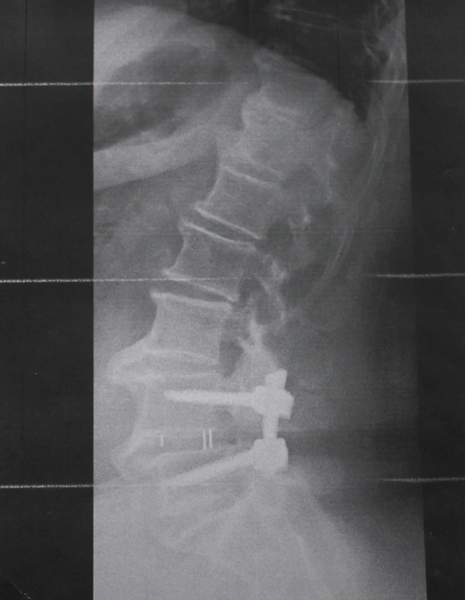

В ходе операции ликвидировали стеноз, освободили спинномозговые нервы, корешки, выполнили декомпрессию и стабилизацию по Хармсу (скрепили позвонки между собой, что позволило стабилизировать их и исключить рецидив заболевания), установили винтовую систему на уровне L4-L5.

В результате получили хороший клинический результат. Операция длилась 1,5 часа с минимальной кровопотерей. Пациентку подняли на вторые сутки после операции. Она расходилась, на пятые сутки сделали рентгеновские снимки, где увидели, что винты стоят правильно, имплант установлен адекватно. На седьмые сутки пациентку выписали, не было температуры и боли. Для таких пациентов реабилитация не требуется, потому что они начинают ходить на вторые сутки после операции.